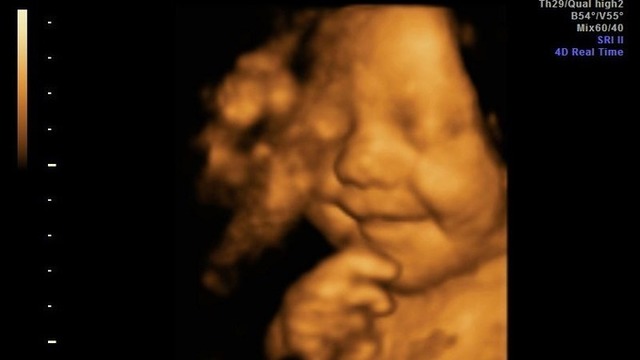

• Semana 33 y 34

Semana 33 y 34

El producto pesa unos 2,200-2,300 kg y mide alrededor de 45 cm. La principal característica de esta etapa es aumento de peso y fortalecimiento de su cuerpo.

El cerebro y el resto de sus órganos principales están finalizando su desarrollo para adaptarse definitivamente, con el fin de llevar sus funciones de manera independiente. El bebé alterna periodos de vigilia y de sueño. El sistema inmunitario es capaz de combatir infecciones leves.Con frecuencia, el bebé tiene hipo y se chupa el dedo.